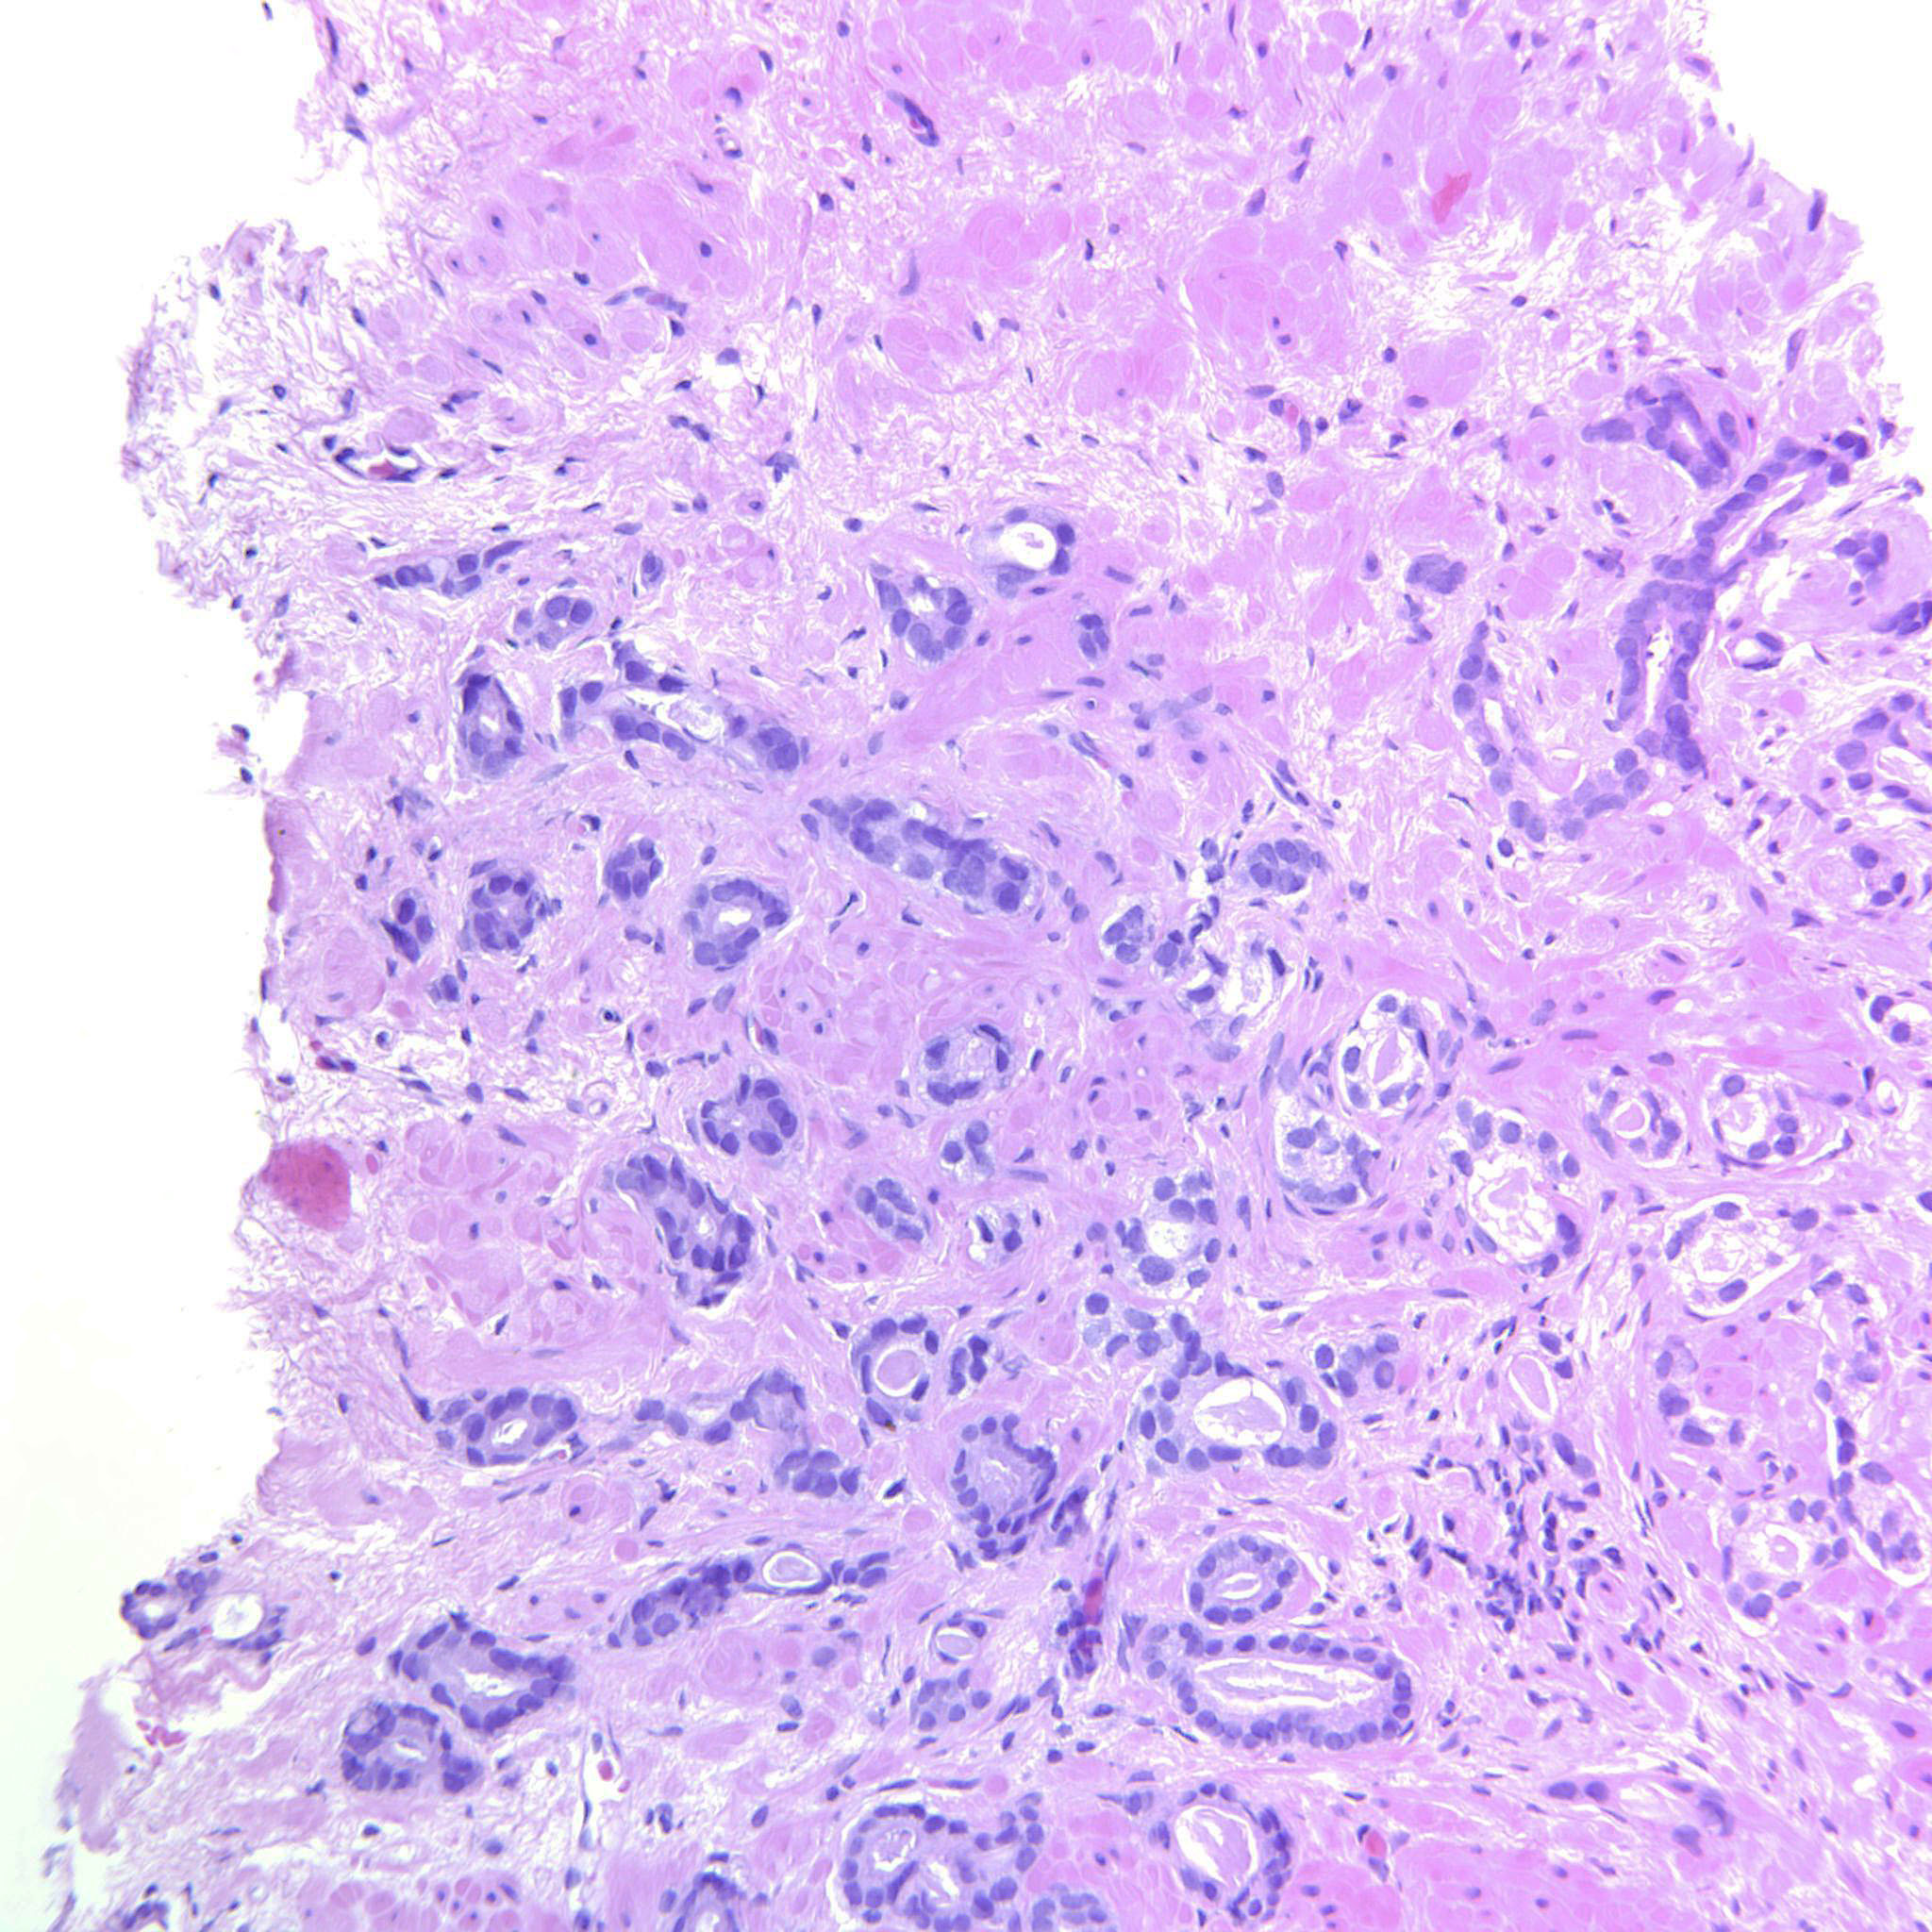

Consensus grade: GS 3+3=6 (ISUP 1)

Case description (by case creator):

Circumscribed cancer glands. Occasional seemingly solid strips of epithelium that may be tangential cuts.